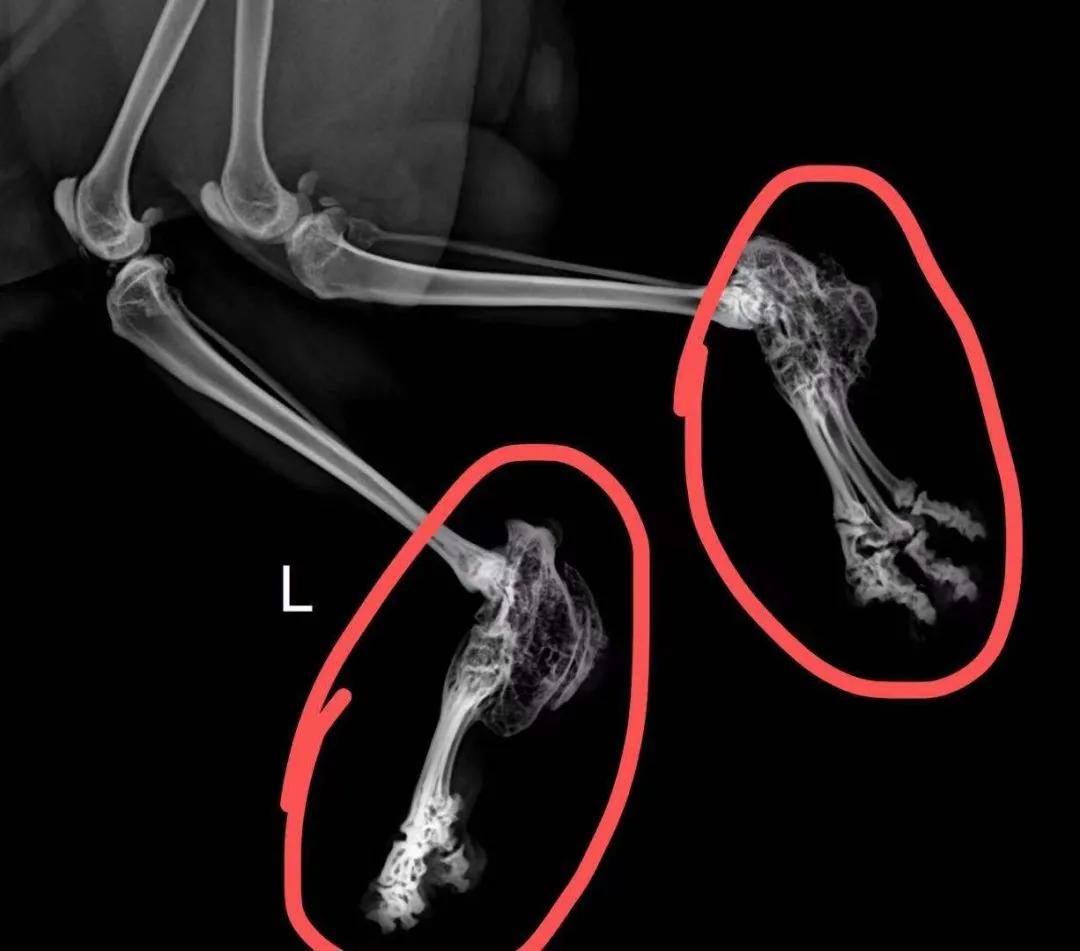

骨损伤

比如骨折、骨裂等情况。

骨关节炎、折耳猫的骨软骨发育不良等,在老年猫中很常见(多数逐渐跛行)。